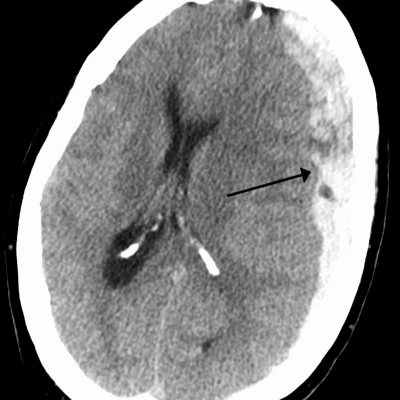

Neurocritical Care Society and Society for Critical Care Medicine recommendations for reversal of antithrombotic agents in patients with intracranial hemorrhage Guideline for Reversal of Antithrombotics in Intracranial Hemorrhage : A Statement for Healthcare Professionals from the Neurocritical Care Society... - PubMed - NCBI http://www.ncbi.nlm.nih.gov/pubmed/26714677 Antithrombotic: Timing, Antidote, Factor Replacement, antifibrinolytics Vitamin K antagonists (warfarin) If INR > 1.3 then Vitamin K 10 mg IV, plus 3 or 4 factor PCC IV (dosing based on weight, INR and PCC type) OR FFP 10–15 ml/kg IV if PCC not available Direct factor Xa inhibitors: activated charcoal (50 g) within 2 h of ingestion, activated PCC (FEIBA) 50 units/kg IV OR 4 factor PCC 50 units/kg IV Direct thrombin inhibitors (dabigatran): Activated charcoal (50 g) within 2 h of ingestion, AND Activated PCC (FEIBA) 50 units/kg IV OR 4 factor PCC 50 units/kg IV Idarucizumab 5 g IV (